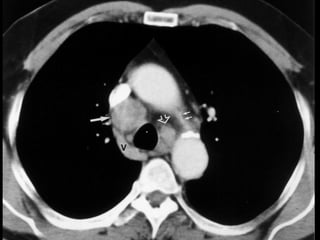

4R. Right lower paratracheal LNs

2R. Right upperparatracheal LNs • Upper border: upper border of manubrium. • Lower border: intersection between lower border of left innominate vein and trachea. • Medial border: midline of the trachea.

4R. Right lowerparatracheal LNs